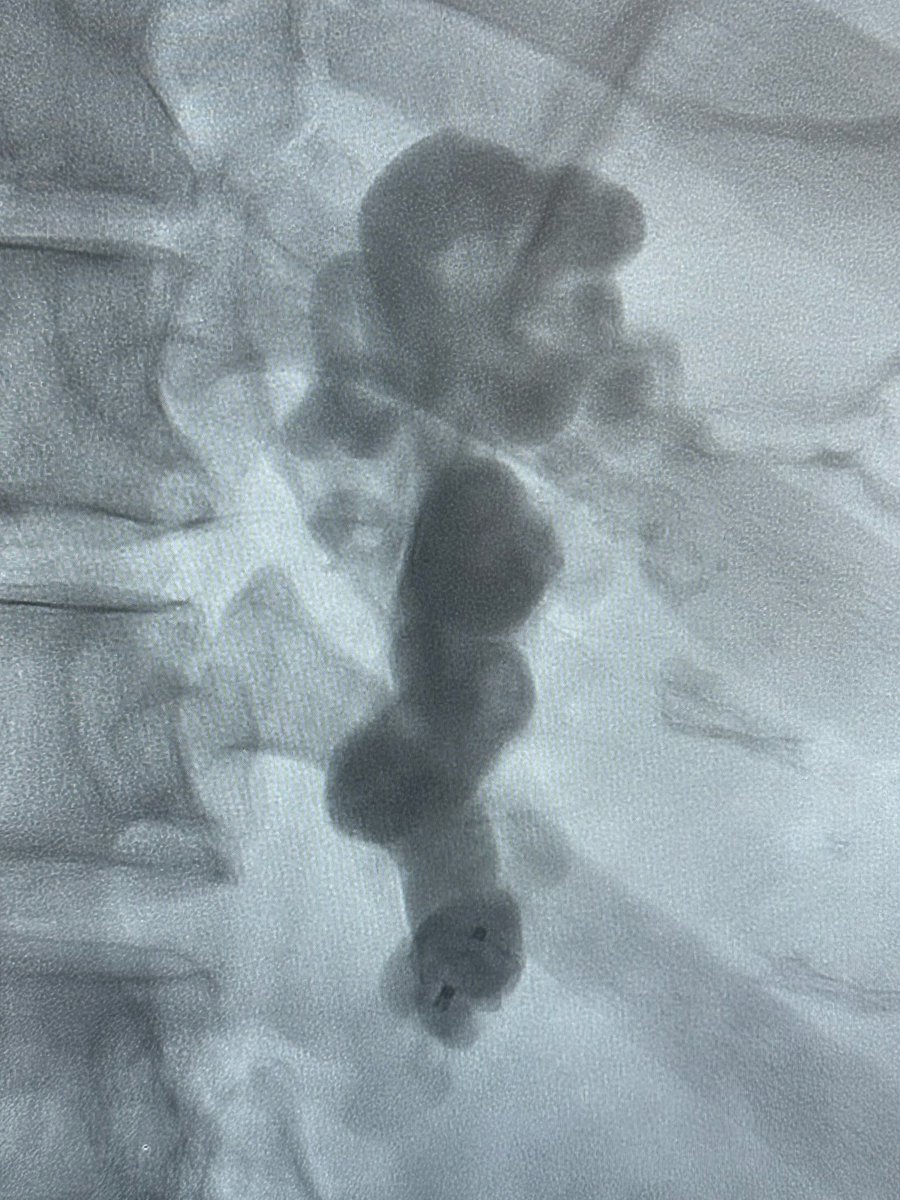

HOT OFF THE PRESS! Neoadjuvant PAE prior to prostate radiation therapy: A single institution experience on the durability of clinical urinary improvement after radiation - ctro.science/article/S2405-… @MoffittNews @MoffittRadOnc @KOSJ12 @gdgrass @VaseemKhatri @ctRO_journal